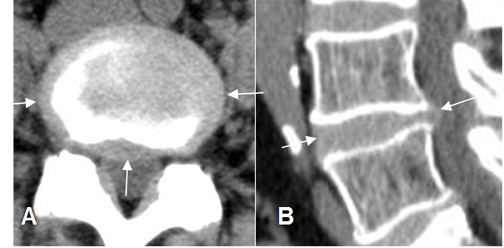

Fig 84. Prominencia del disco.

A: TAC axial y B: TAC reconstrucción sagital. El disco supera los bordes de la vértebra, de forma simétrica, por prominencia.